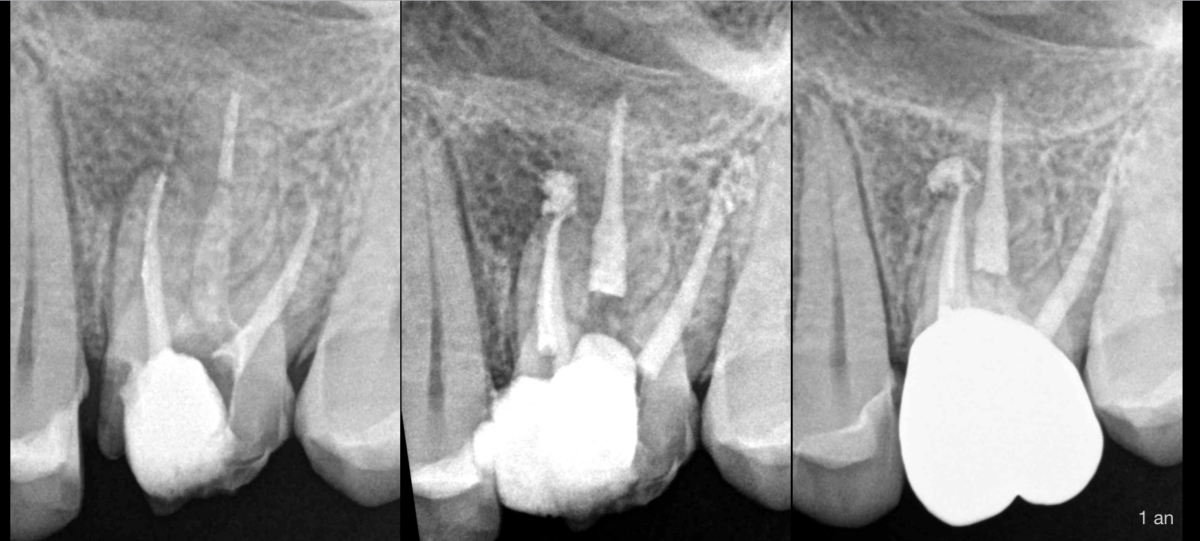

🔍 Pulpe précédemment traitée, parodontite apicale symptomatique (racine MV).

MV2 non traité.

➡️ Retraitement canalaire.

Même dans le cas où la perméabilité de tous les canaux a été obtenue, et que le maximum de désinfection a été apporté dans les meilleures conditions possibles : 𝐩𝐨𝐮𝐯𝐨𝐧𝐬-𝐠𝐚𝐫𝐚𝐧𝐭𝐢𝐫 𝐚̀ 𝐧𝐨𝐭𝐫𝐞 𝐩𝐚𝐭𝐢𝐞𝐧𝐭 𝐪𝐮𝐞 𝐥𝐞 𝐭𝐫𝐚𝐢𝐭𝐞𝐦𝐞𝐧𝐭 𝐬𝐞𝐫𝐚 𝐞𝐟𝐟𝐢𝐜𝐚𝐜𝐞 𝐚̀ 𝟏𝟎𝟎% ?